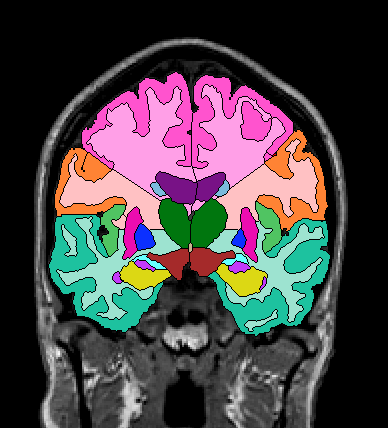

The insular cortex is “hidden” between the temporal and inferior parietal corticies. By drawing sulci lines in the sagittal view, we gain an outline of it in the coronal. Choose a sagittal slice where insula is clearly visible (Fig 1), then draw a “circle” around it (Fig 2). Do this for several slices and for both hemispheres.

Figure 1              Figure

2